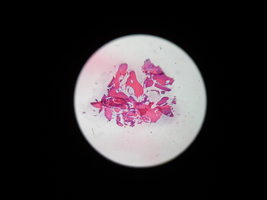

Морфологическое и лабора-торное обоснование приме-нения комбинированных трансплантатов при костной пластике челюстей

Экспериментальное исследование. Изучение морфогенеза после заме-щения дефектов нижней челюсти смесью лиофилизированной алло-спонгиозы и “аллогенного гидроксиапатита” в соотношении 1:1 и 3:1.

Экспериментальное исследование. Изучение морфогенеза после заме-щения дефектов нижней челюсти смесью лиофилизированной алло-спонгиозы и “аллогенного гидроксиапатита” в соотношении 1:1 и 3:1.